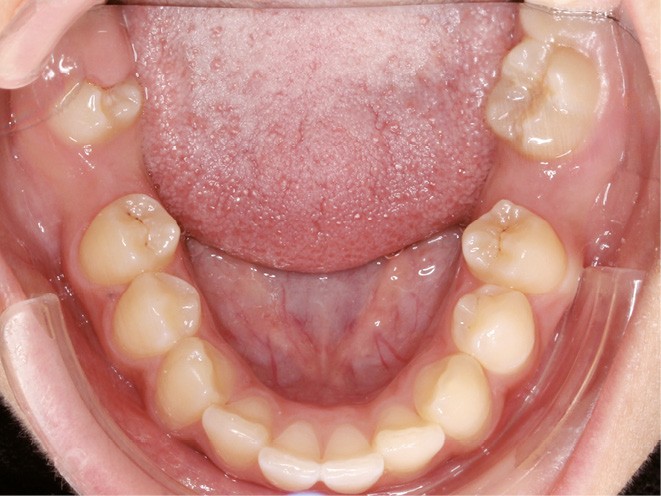

Examen endobuccal (fig. 2a-e)

L’hygiène est satisfaisante et le parodonte sain. On note aux deux arcades l’absence des premières molaires et la fermeture partielle des espaces d’extraction avec mésiorotation marquée de 17, 27 et 37. À la mandibule, l’encombrement antérieur est estimé à 2 mm et les espaces d’extraction résiduels à 12 mm.

Dans le sens transversal, malgré une occlusion correcte des secteurs latéraux, on observe une endoalvéolie maxillaire et une non-concordance des médianes incisives avec déviation de la médiane mandibulaire vers la droite. Le recouvrement incisif est normal.